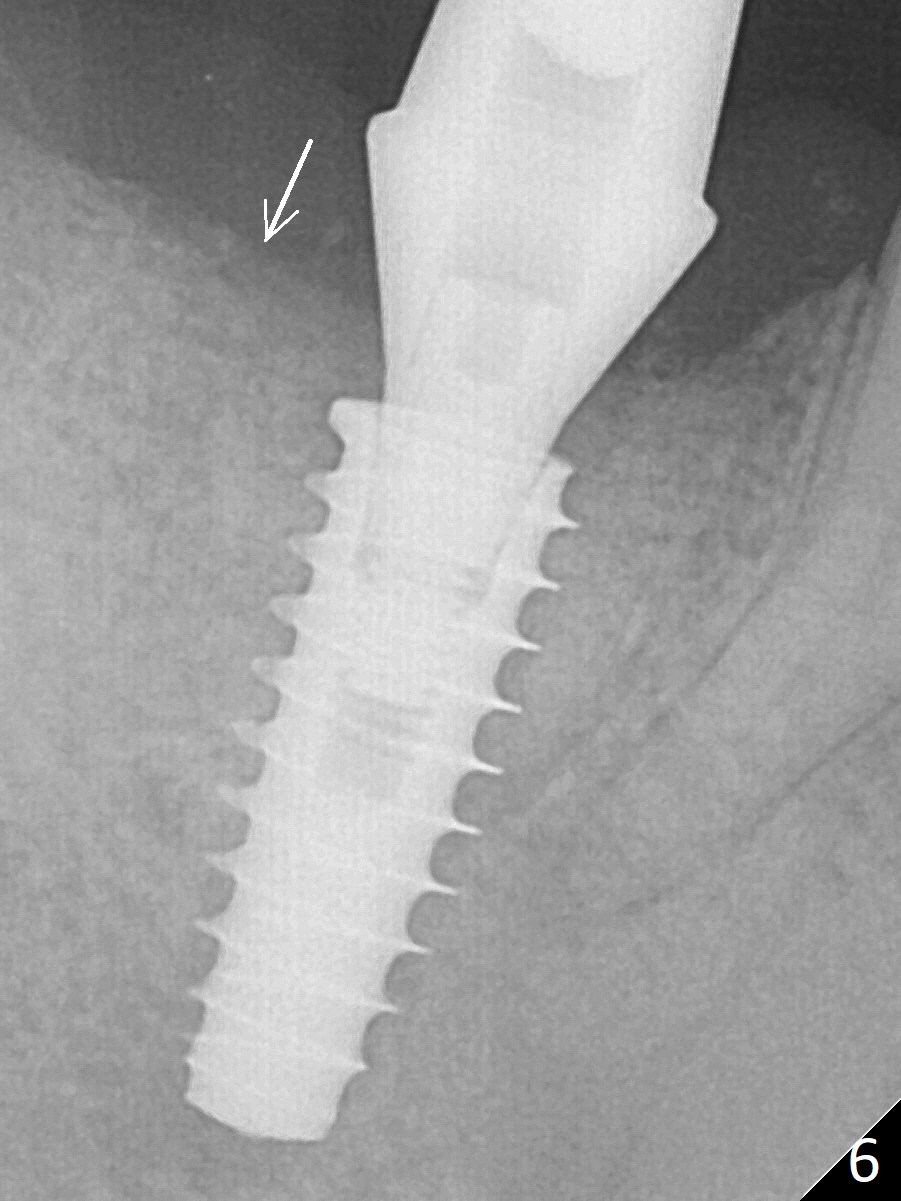

Bone graft seems to sink down and becomes denser 3 months postop (Fig.6 arrow). The bone continues being denser 5 months postop (Fig.7). There is periapical radiolucency of the tooth #29 (^).